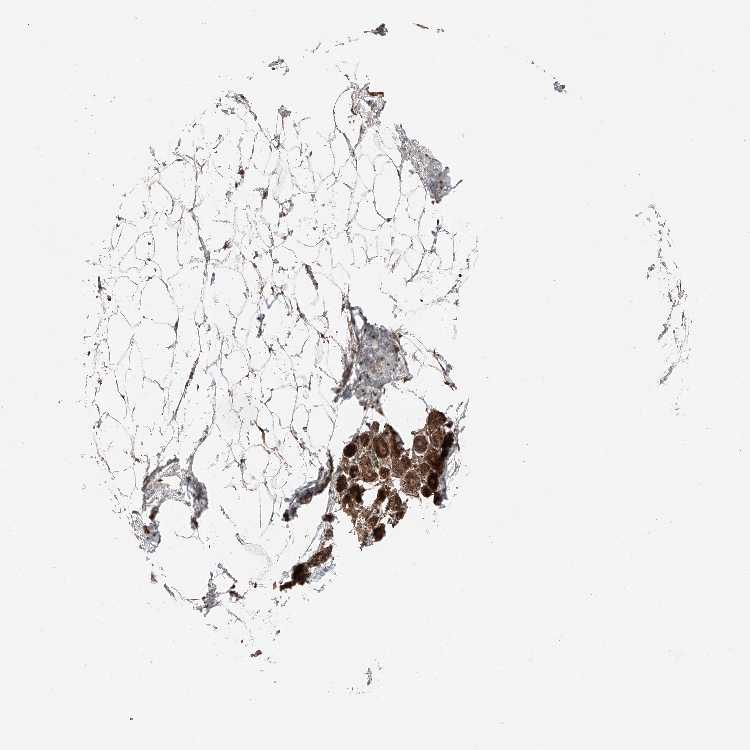

BREAST - Antibody stainingi

Antibody staining in the annotated cell types in the current human tissue is reported as not detected, low, medium, or high, based on conventional immunohistochemistry profiling in selected tissues. This score is based on the combination of the staining intensity and fraction of stained cells.

Each image is clickable and will lead to virtual microscopy that enables deeper exploration of all samples and also displays staining intensity scores, fraction scores and subcellular localization as well as patient and tissue information for each sample.

Antibody HPA007241Antibody HPA011109

Adipocytes MediumNot detected

Glandular cells HighHigh

Myoepithelial cells HighMedium